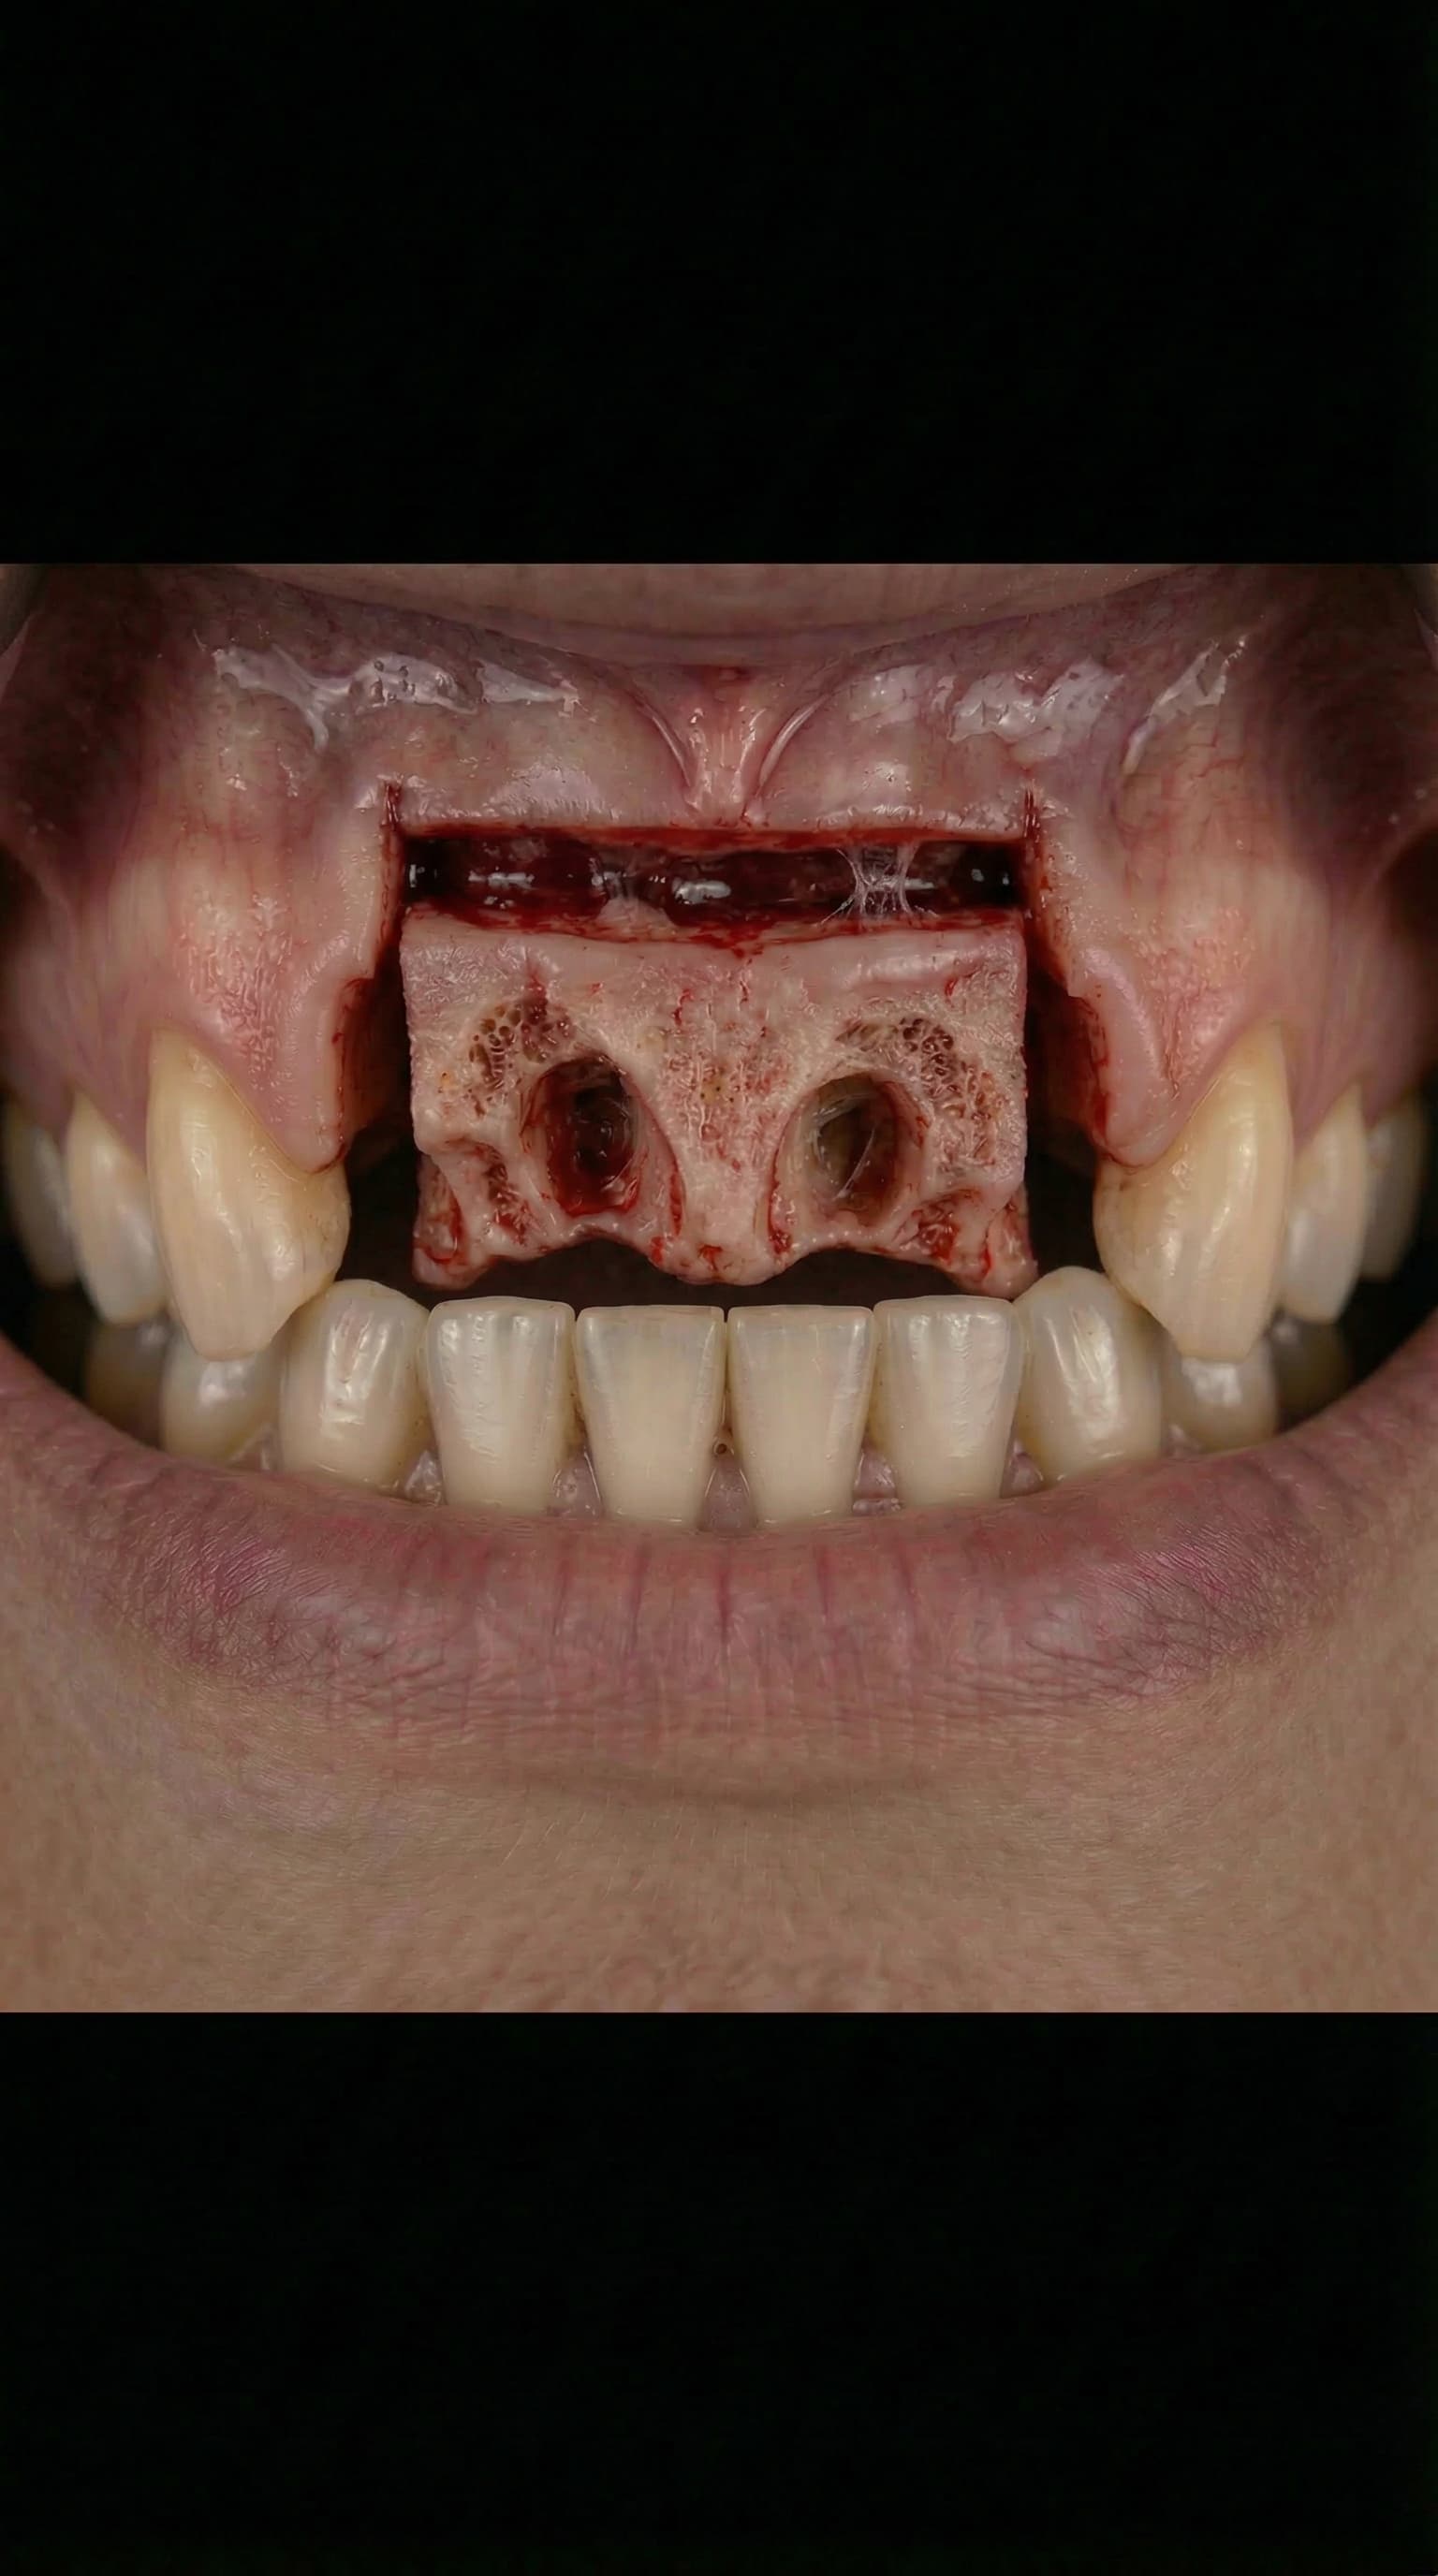

Extraction Socket

The Dental Implant Journey — from extraction to your new permanent smile

Bone Grafting & Sinus Lifts

Advanced bone regeneration using organic and holistic bone grafting materials to rebuild jawbone lost to tooth extraction, periodontal disease, or trauma. Dr. Antipov performs sinus lift surgery (sinus augmentation), ridge augmentation, socket preservation, block bone grafts, and guided bone regeneration (GBR). We offer autogenous (your own bone), allograft, xenograft, and synthetic bone graft options — including minimally processed, naturally derived materials for patients who prefer a holistic approach to dental implant preparation.